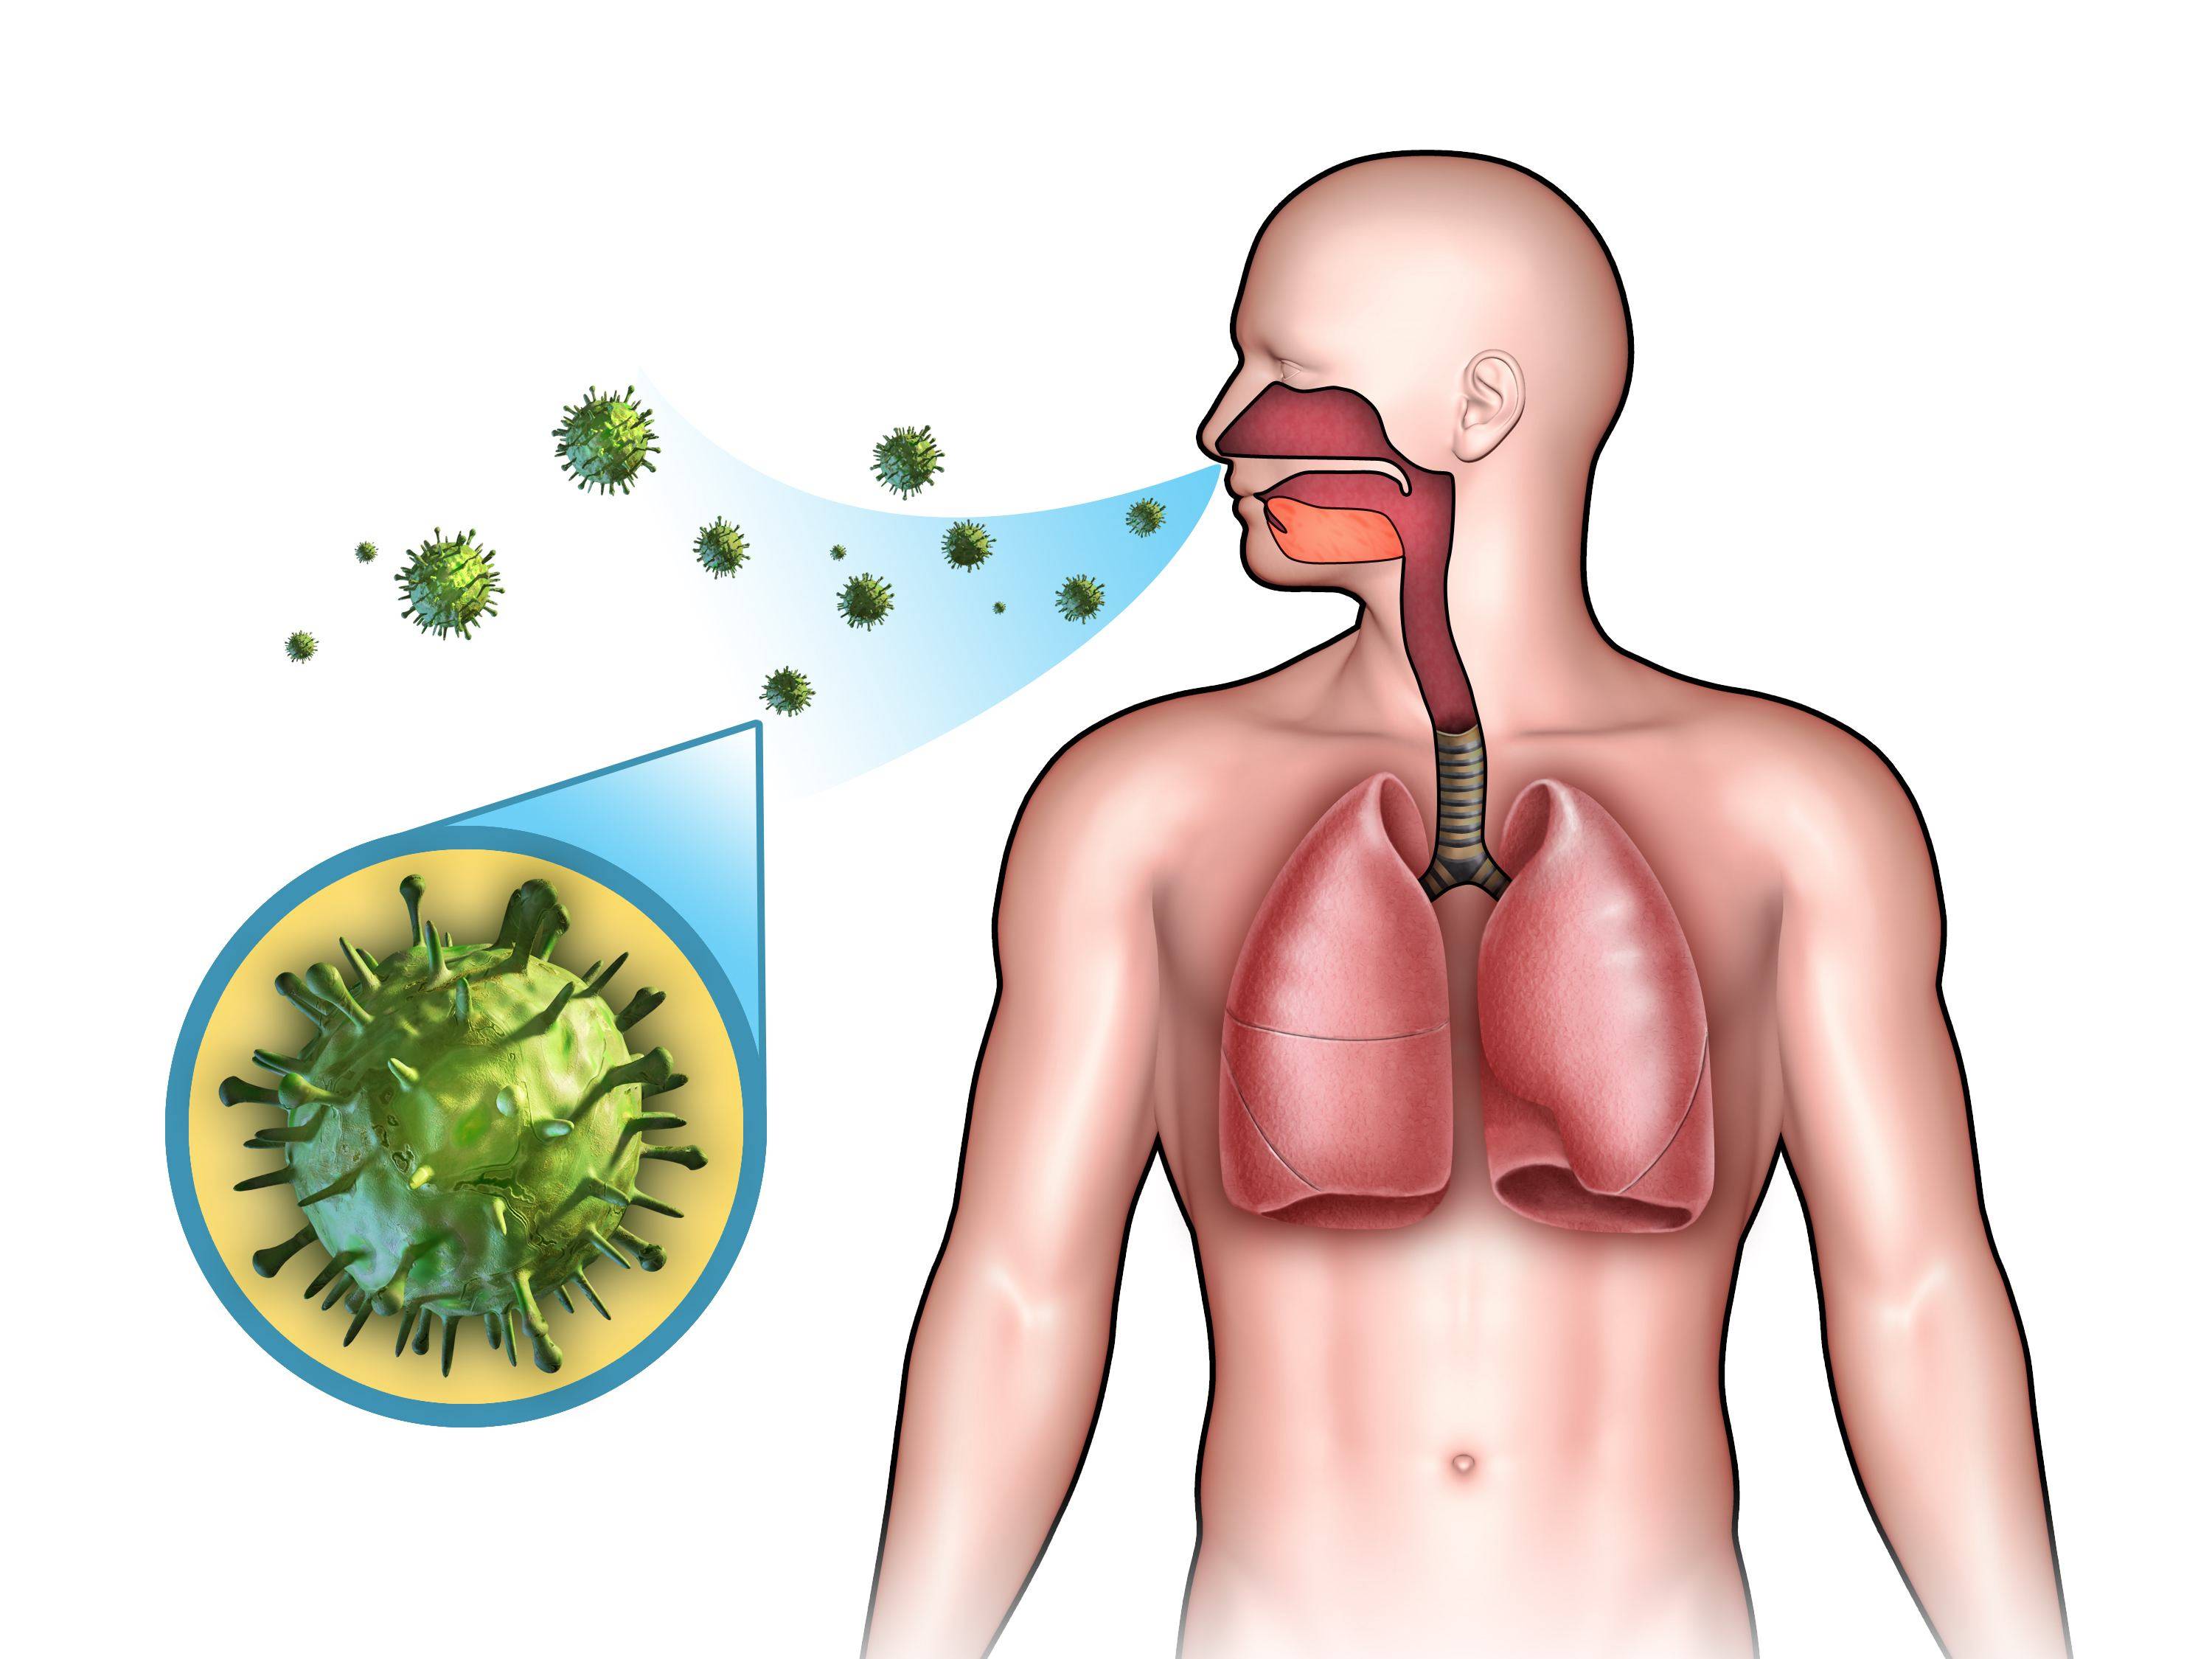

Иконки респираторных заболеваний: набор для медицинских приложений